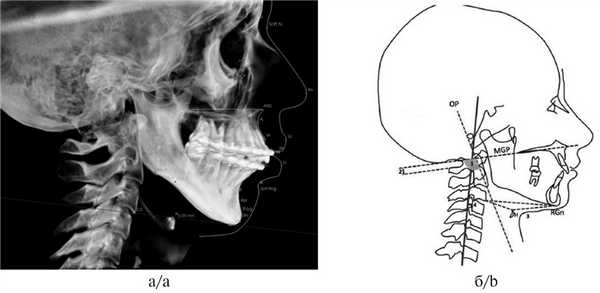

III. Анализ краниомандибулярных нарушений (необходим при планировании комплексного лечения совместно с миофункциональным терапевтом) и оценка объема дыхательных путей для исключения синдрома обструктивного апноэ. Оценка положения подъязычной кости (краниоцервикальный цефалометрический анализ по M. Rocabado) и языка. Измерение проводится следующим образом: необходимо провести линию от передненижнего угла тела III шейного позвонка к наиболее нижней точке подбородочного симфиза Me (Menton), далее к начерченной линии проводят перпендикуляр от наиболее передней и верхней точки подъязычной кости. В норме длина перпендикуляра должна составлять 5,0±2,0 мм (рис. 6).

Рис. 6. Подъязычный треугольник по M. Rocabado (а) и оценка положения подъязычной кости к основанию тела нижней челюсти (0,09 мм) (б).

3. Оценка положения шейных позвонков (краниовертебральные функциональные пространства по M. Rocabado). В норме расстояние между C0—CI (затылочная кость и I шейный позвонок) и CI—CII (остистыми отростками I и II шейных позвонков) — 6,5±1—2,5 мм (рис. 8) [14].

4. Краниовертебральное центральное соотношение по M. Rocabado. На КЛКТ также есть возможность анализа ротаций первого и второго шейных позвонков. Измерение проводят от заднего бугорка первого шейного позвонка к зубу второго шейного позвонка, при этом большее расстояние свидетельствует о ротации CI в данную сторону (рис. 9).

Рис. 9. Ротация первого шейного позвонка (CI) вправо, так как расстояние между CI и зубом CII больше с правой стороны — 5,09 мм; слева — 3,43 мм.